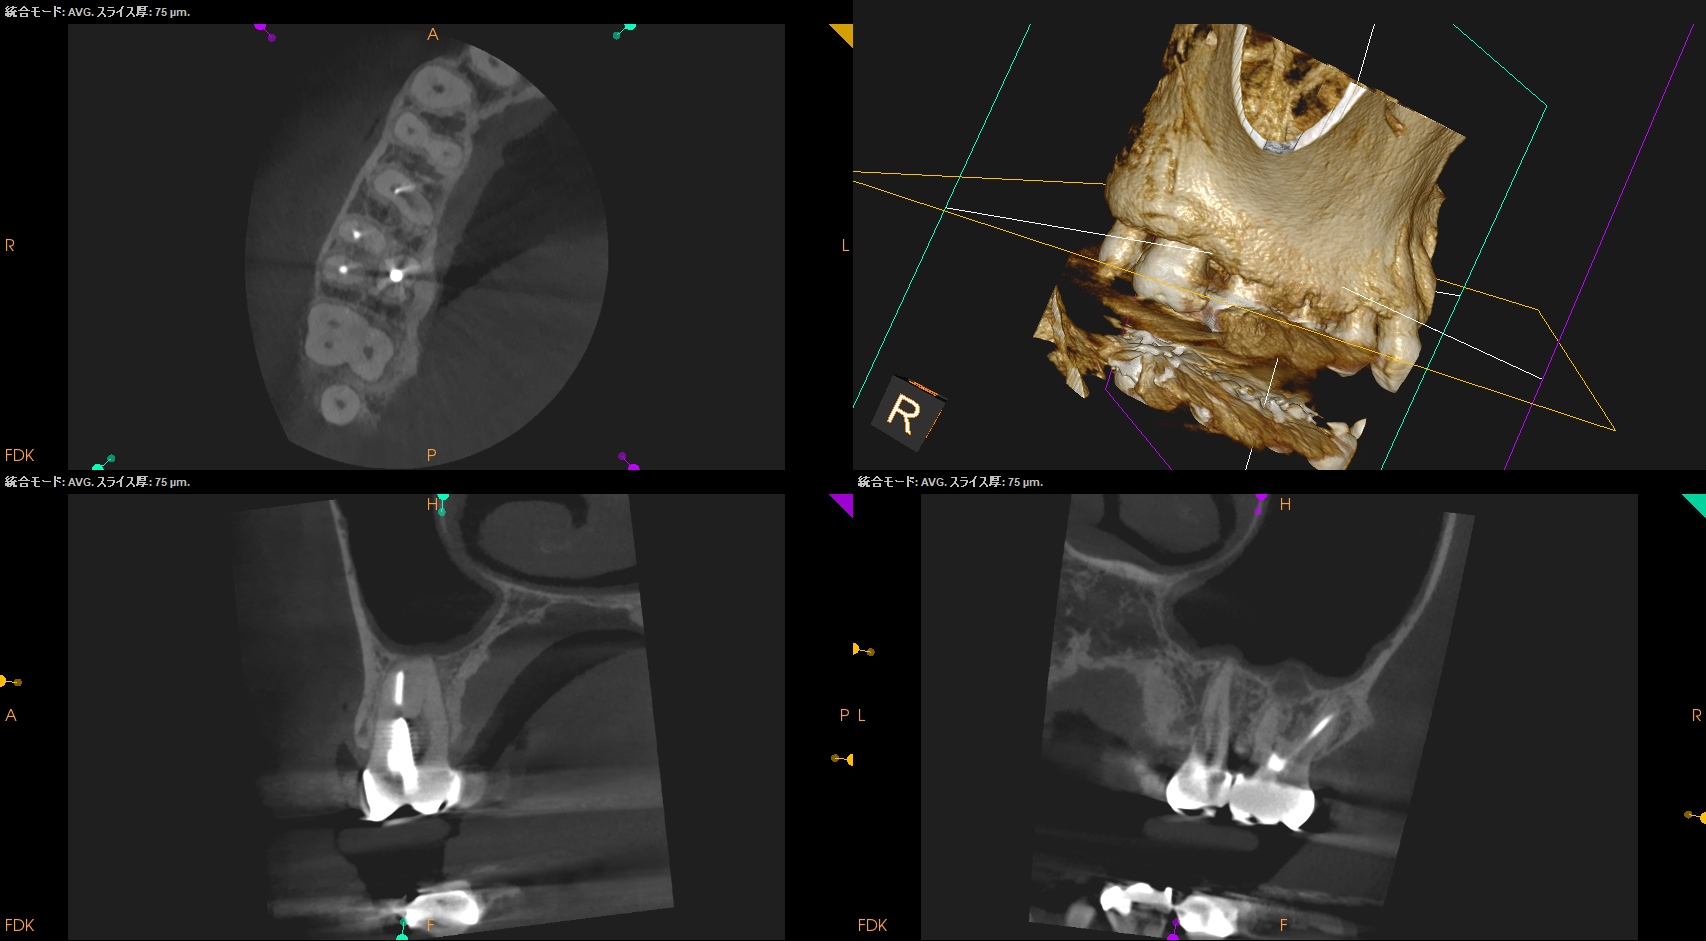

CBCT(2025.9.1)

#3

MB

DB

P

#4

B

#3に関してだが、MBの破折ファイルはちょうどカーブの変曲点を超えて根尖部に折れ込んでいる。

この時点で、それをいかにして除去するか?よりも、FileごとApicoectomyしたほうが時短になると私は考える。

CEJよりも10mm下方にMBのApexがあり、

破折したファイルごと除去しようと思えば3mmでなく4.5mmApexから切断したほうがいいだろう。